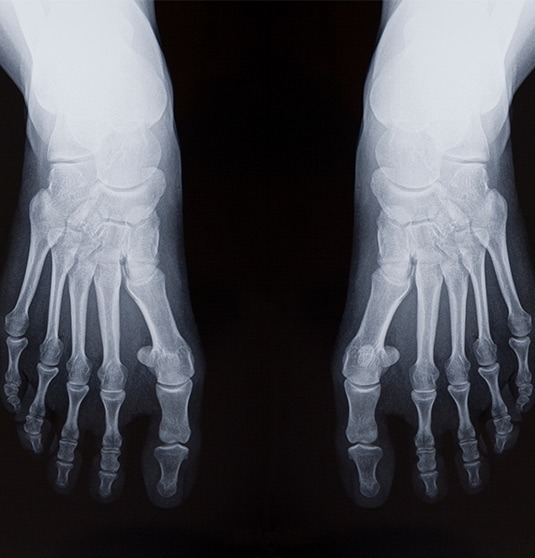

Ein Spreizfuss kann einen oder beide Füsse betreffen und verursacht oft Probleme und Symptome, die den Alltag und die Lebensqualität beeinträchtigen. Unbehandelt kann sich die Fehlstellung des Fusses auf den gesamten Körper auswirken.

Schauen wir uns die Ursachen, Auswirkungen und Behandlungsmöglichkeiten des Spreizfusses einmal genauer an: